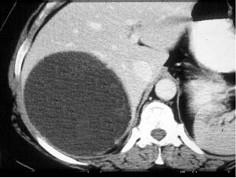

下列图像最可能的诊断是 ( )A.脂肪肝B.肝囊肿C.肝血管瘤D.肝脓肿E.肝炎肝硬化

问题 下列图像最可能的诊断是 ( )

选项 A.脂肪肝 B.肝囊肿 C.肝血管瘤 D.肝脓肿 E.肝炎肝硬化

答案 B